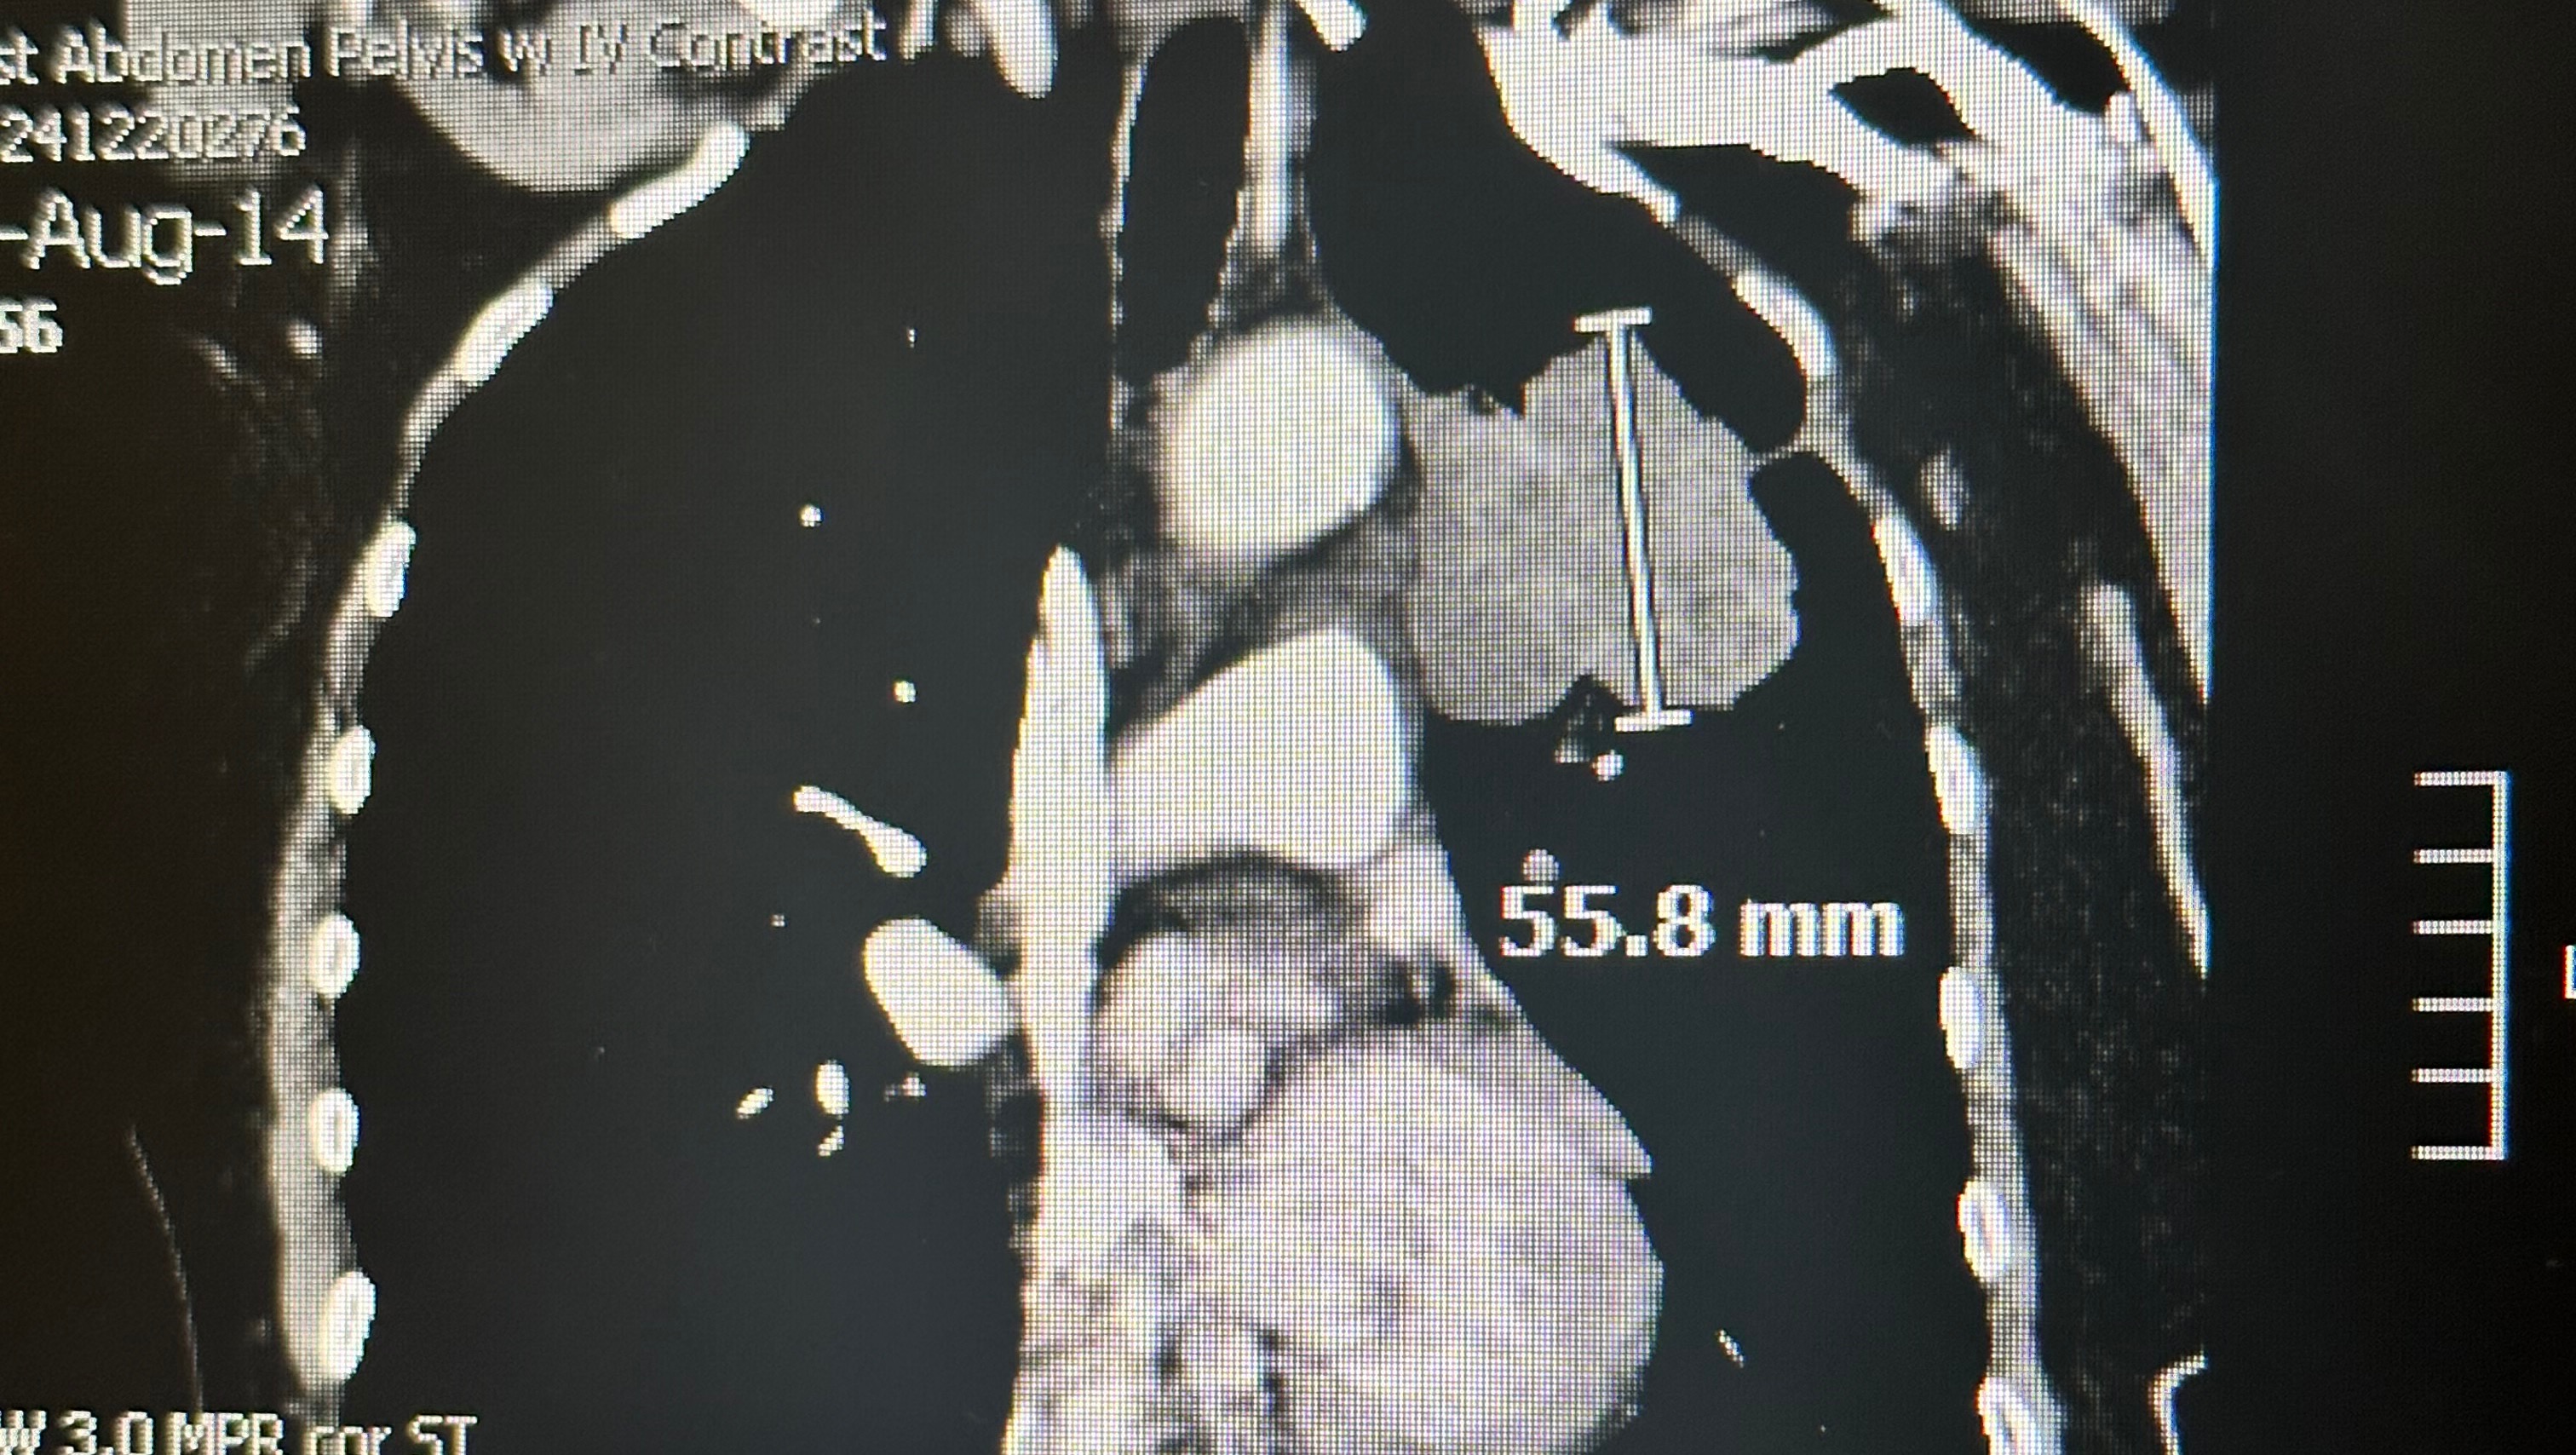

Our beloved Viola, also known as Cissy, recently endured a life-changing event. On August 12, 2024, she was involved in a car accident that led to a series of unforeseen and heartbreaking discoveries. The following day she went to Medstar St. Mary’s Hospital, for just a head injury and stitches. They ordered an MRI and CT scans to be done and revealed a cancerous brain tumor and lung cancer. Cissy was airlifted to Georgetown University Hospital, where she underwent emergency surgery to remove the brain tumor.